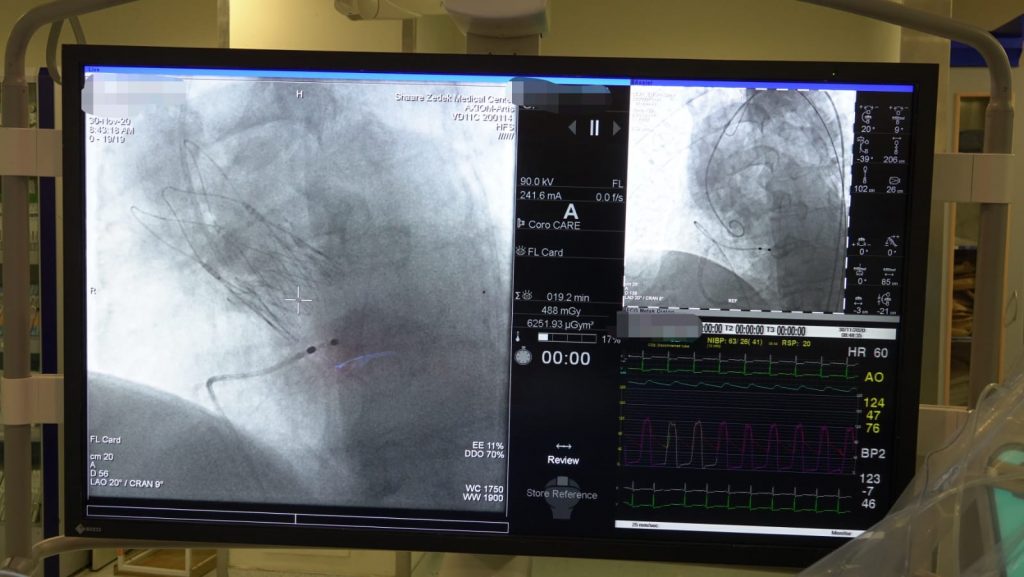

במרכז הלב המשולב במרכז הרפואי שערי צדק, בוצעה אתמול לראשונה בישראל השתלת מסתם חדש בגישה מלעורית (TAVI) שמהווה דרך חדשה לטיפול מיטבי בחולים מורכבים הסובלים מהיצרות קשה של המסתם האאורטלי ללא התערבות כירוגית.

את ההשתלה ביצע מנהל יחידת הצנתורים בשערי צדק, ד"ר ירון אלמגור יחד עם צוות היחידה.

מכון הצינתורים במרכז הלב המשולב בשערי צדק נבחר למרכז הראשון בישראל ומהראשונים בעולם בו יושתל המסתם החדש.